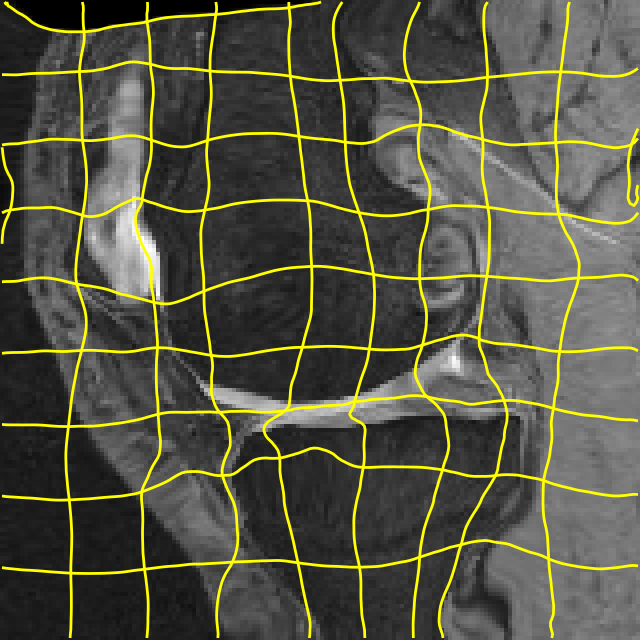

Moving Target Mono-0 Mono-21 DA-1 DA-21 Mono-65 Refer to caption Refer to caption Refer to caption Refer to caption Refer to caption Refer to caption Refer to caption Refer to caption Refer to caption Refer to caption Refer to caption Refer to caption Refer to caption Refer to caption

Figure 4: Examples of brain MRI registration (top) and knee MRI segmentation (bottom) results. Top: The first two columns are the moving image/segmentation and the target image/segmentation followed by the warped moving images/segmentations by different models. Bottom left to right: original image, manual segmentation, and predictions of various models. Mono-i𝑖i and DA-i𝑖i represent the mono- and DA models trained with i𝑖i manual segmentations respectively.